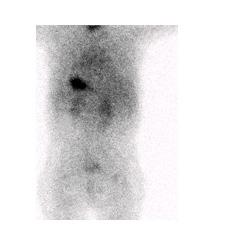

Figure 8 : Patient de 8 ans avec douleur abdominale, rectorragie, lipothymie. Examen effectué après préparation préalable avec Ranitidine IV. L’étude dynamique ( A ) puis le cliché statique ( B ) révèle un foyer de captation près des vaisseaux iliaques droits qui augmente au cours du temps (flèche). Le diverticule et la captation du traceur sont revus sur l’étude SPECT-TDM (C). Un Meckel de 5 cm contenant de la muqueuse grêle et gastrique a été trouvé à la chirurgie.

Interprétation

Le diverticule de Meckel apparait comme une captation focale le plus souvent au quadrant inférieur droit (figure 8). La captation apparait souvent dans les 5 à 10 minutes après l’injection en parallèle avec l’estomac et peut apparaitre dès la première minute. La captation augmente en intensité avec le temps, typiquement au même rythme que la captation gastrique alors que l’activité rénale démontrée dans les 2-3 premières minutes va diminuer (figure 9).